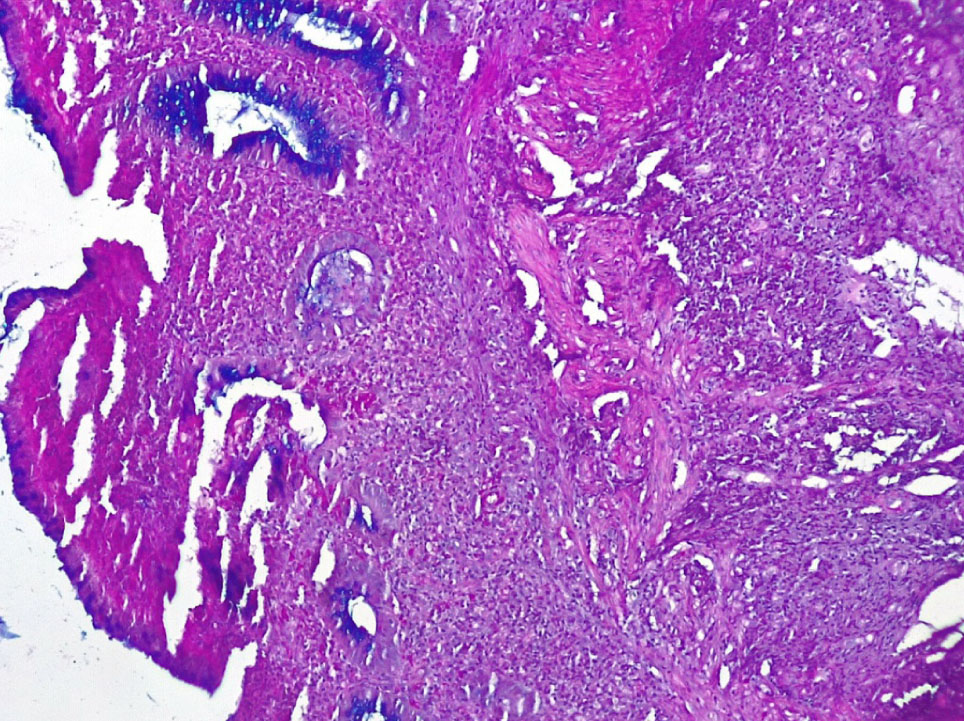

В отдельных группах крипт отмечалось выраженная атрофия бокаловидных клеток (БК) (не более 3–4 на крипту) вплоть до полного их исчезновения (+++), развитие очагов гнойного криптита за счет выраженной нейтрофильной инфильтрации вокруг крипт (рис. 4).

Рис. 4. Основная группа: неравномерная атрофия крипт и бокаловидных клеток СО толстой кишки, выраженное хроническое воспаление стромы со скоплением нейтрофилов в отдельных криптах (гнойный криптит). Окр. гематоксилин-эозином, ×200

В отдельных участках СО при НЯК встречались единичные крипты, содержащие отдельные бокаловидные клетки и альциан + гликопротеиды (нейтральные мукополисахариды), резко выраженное хроническое воспаление стромы с развитием рыхлой волокнистой соединительной ткани (фиброза) (+++ степень атрофии и фиброза) (рис. 6).

Рис. 6. Основная группа: в СО при НЯК отмечается резкая атрофия крипт и бокаловидных клеток, содержащих незначительное количество альциан + муцина. ШИК-реакция с докраской альциановым синим, ×200